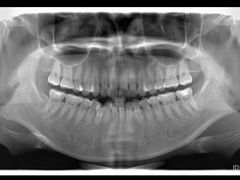

• 固瑞齿科(国贸门诊店)

• -固瑞齿科(国贸门诊店)